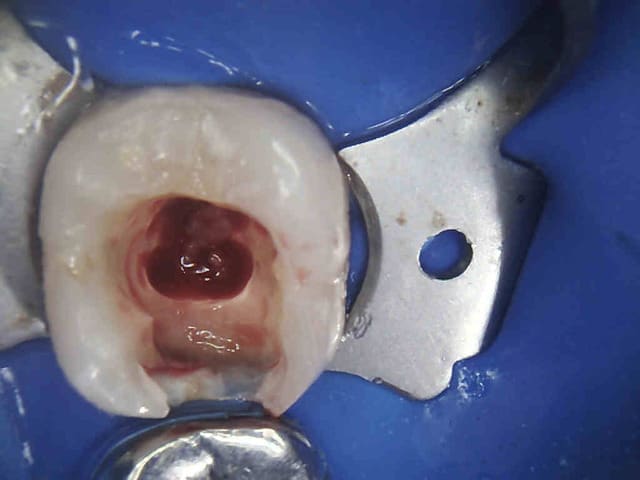

Tiens mon choupinet mutualiste.-))))

Au fait, t'as oublié la digue, pour ton compo. Une merde, quoi...

Pour la digue, sur les endos molaire seulement, il existe d'autres moyens moins chiants à poser pour les compos, il est en effet autrement plus chiant de poser la digue sur une demi arcade et surtout de façon compatible avec les matrices ( le v3 ring n'aime pas les clamps à ailettes). Mais tu devrais le savoir non ?

J'y travaille pour trouver un moyen simple et efficace pour poser la digue dans toutes les situations comme celle ci dessous. Tiens c'est tout frais, endo sc33 en 1 temps, 1H 15 et encore je n'ai pas d'assistante au fauteuil.

Pulpite indication endo. perte de substance: Indication onlay , mais pas dans le panier de soins donc sc 33, couronne coulée : patiente CMU.

Dis donc chicot t'es peut être le roi de l'endo mais au niveau économie tissulaire , ouverture de chambre , tu utilises un black et decker comme contre angle ?... t'y vas pas de main morte ... t'aurais peut être pu éviter le tenon alors , et qui sait la couronne .... et puis un genre screw post titane ? avec un matériau plastique perso je trouve pas ça terrible ... mais je ne suis qu'une petite dentiste qui utilise encore l'amalgame ... houuuu la méchante .....bon et puis la (ou le ) mitrailler comme ça pendant le soin juste pour nous montrer , faut pas tu sais , tu perds un temps fou ... après le temps de poster tout ça ..... t'imagines le temps perdu pour la rentabilité du cabinet ....